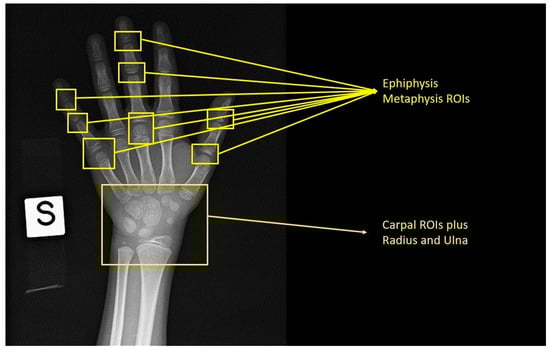

The Tanner Whitehouse Method (1983) (TW2) [11] assesses the level of maturity of 20 selected regions of interest in specific bones of the hand and wrist in each age population. The development level for each region of interest is categorized into specific stages (from A to I) corresponding to a numerical score for every single bone. A global sex-specific maturity score is then obtained by summing all the individual scores and converting them into bone age [51].

Despite the higher accuracy and reproducibility compared to the atlas-based techniques, the Tanner Whitehouse Method is more complex and time-consuming (Figure 1) and the classification is sometimes ambiguous as a particular bone shape can have two different predefined labels of the same feature [18].

Figure 1. Tanner Whitehouse Method (TW2) with a demonstration of the region of interest that should be placed for age calculation.